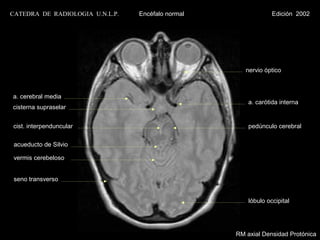

CATEDRA DE RADIOLOGIA U.N.L.P.   Encéfalo normal                Edición 2002

nervio óptico

a. cerebral media

a. carótida interna

cisterna supraselar

cist. interpenduncular                                 pedúnculo cerebral

acueducto de Silvio

vermis cerebeloso

lóbulo occipital

RM axial Densidad Protónica